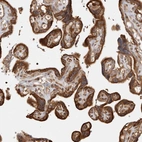

Immunohistochemical staining of human cerebral cortex, placenta, prostate and testis using Anti-CAMSAP2 antibody HPA027302 (A) shows similar protein distribution across tissues to independent antibody HPA026304 (B).